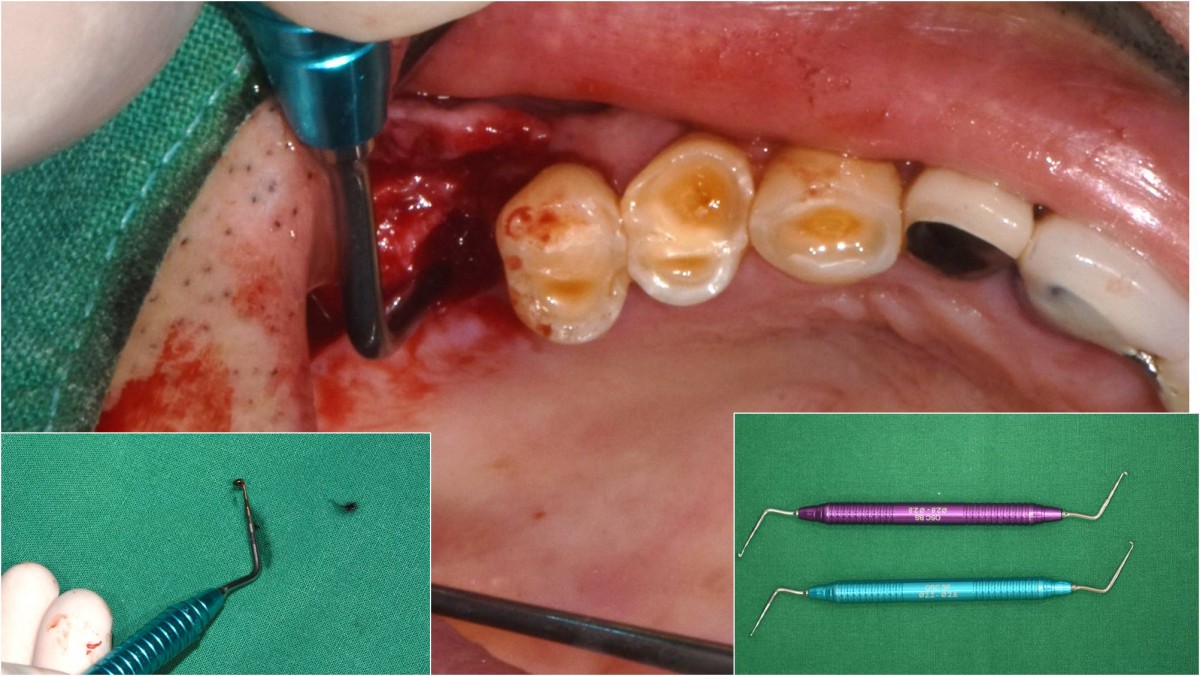

Socket Lift and Implant Placement in the right maxilla.

<GCacg> A 56-year-old male patient complained of pain in the right upper and lower jaws. And he wanted the upper first molar to be pulled out first.